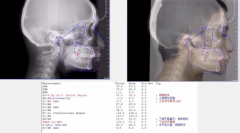

文夫医生分析矫治方案应如何制定

想做牙齿矫正,但是矫正方案怎么设计才是适合自己的呢?正畸医生又是如何制...【详细】